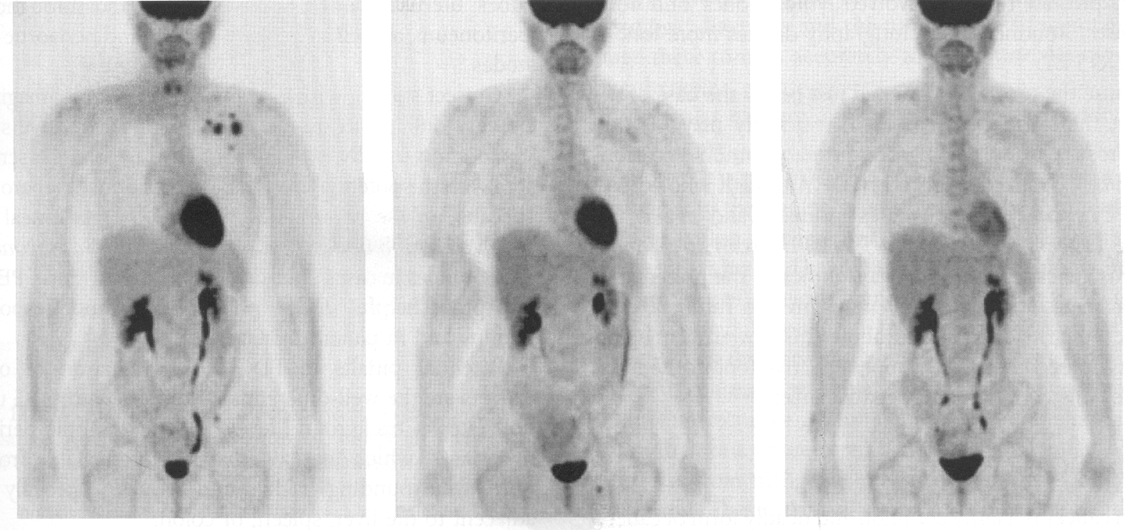

this image shows pre and post breast cancer monitoring (pre and post chemotherapy)

the image on the left is initial, 3 months or 5 months

initial

the image in the middle is initial, 3 months or 5 months

3 months

the image on the right is initial, 3 months or 5 months

5 months